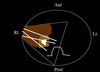

what are the arrows pointing to?

What can you see if the bladder is hydrated?

The extrarenal pelvis medial to the kidney on transverse scans